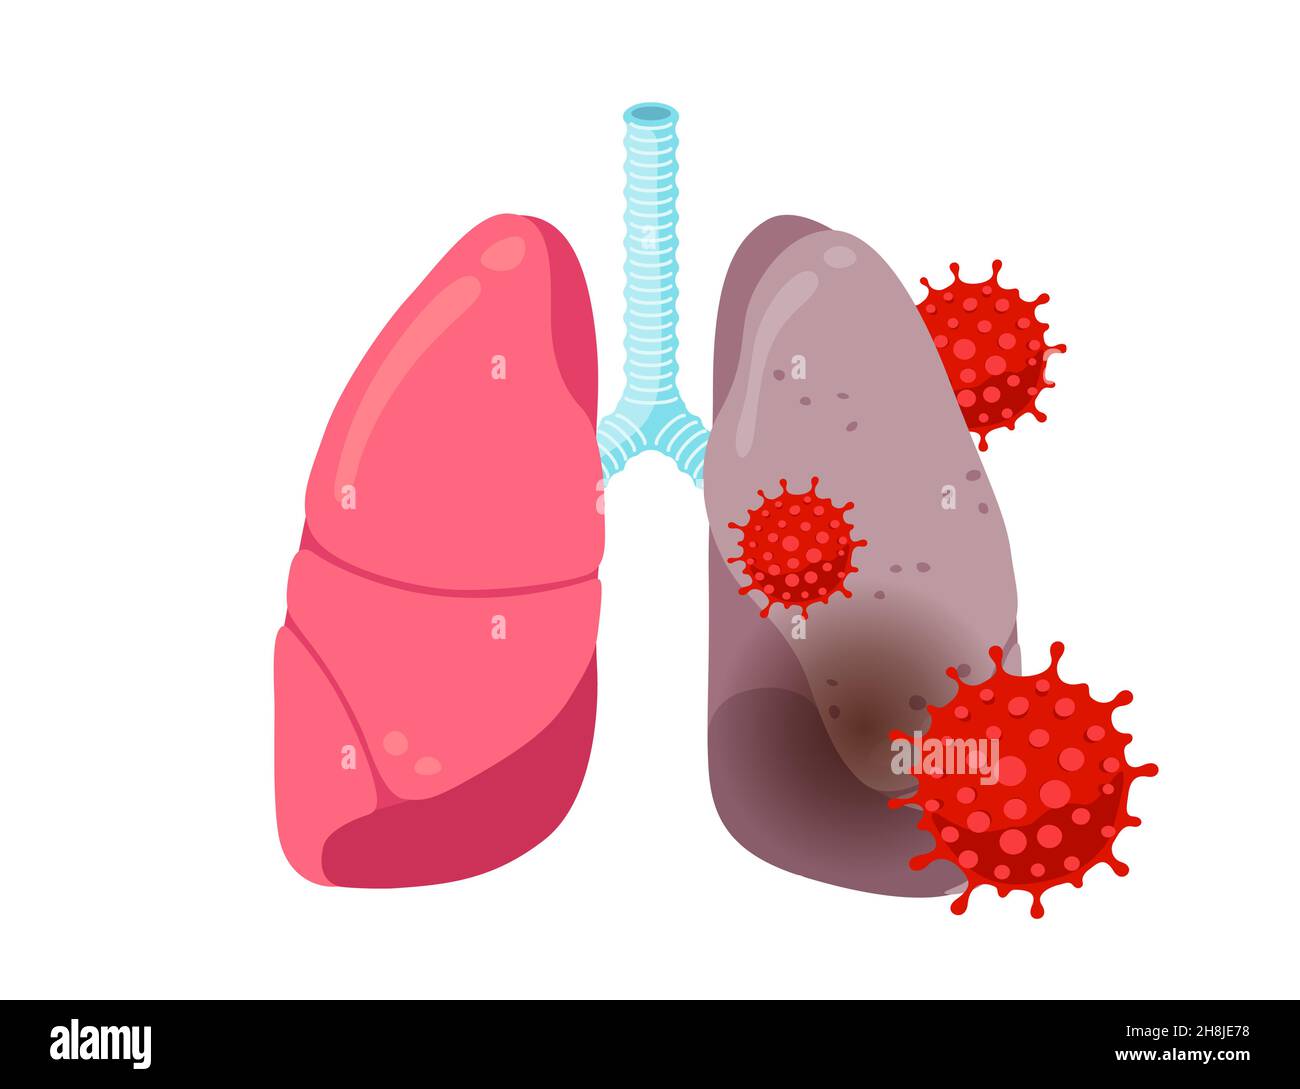

Lista es una colección y muestra de imágenes sobre imagenes de pulmones sanos y enfermos realizada por upup.edu.vn. Además, hay imágenes relacionadas con imagenes de pulmones sanos, imágenes de pulmones sanos, radiografía de pulmones sanos y enfermos, fotos de pulmones sanos, radiografía pulmones sanos y enfermos, rayos x de pulmones sanos y enfermos, pulmon sano y enfermo, pulmón sano y enfermo . Para más información, consulta a continuación.

imagenes de pulmones sanos y enfermos

Posts: imagenes de pulmones sanos y enfermos